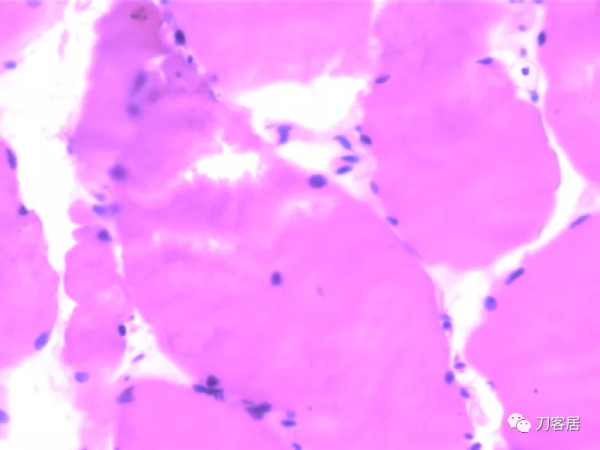

患者發病後右腿腓腸肌病理切片所見:灰紅色至綠豆大組織四塊。光鏡檢查結果:病理診斷“右側腓腸肌”肌纖維肥大變性,個別肌纖維可見溶解及空泡。患者家屬拒絕屍檢。

(6)病理學檢查右側腓腸肌肌纖維粗細不均,肌細胞漿溶解,縱橫紋不清晰,有纖維肥大變性,個別肌纖維可見溶解及空泡。根據以上特點,此患者可診斷MH。

患者發病後